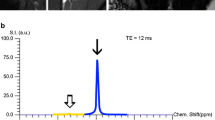

MR imaging of the right shoulder was performed at a 3.0 T MR scanner (Magnetom Vida, Siemens Healtineers) using a dedicated 16-channel shoulder coil (Shoulder Shape 16, Siemens Healtineers). The arm was positioned in neutral zero position. For chemical shift encoding-based water-fat separation of the RC, a transverse-prescribed two-point T1w Dixon sequence was acquired with the following parameters: repetition time (TR) = 4.2 ms, echo times (TE) = 1.23 and 2.46 ms, flip angle = 5°, GRAPPA factor = 2, voxel size = 0.7 × 0.7 × 3.0 mm3, phase encoding direction = A/P, consecutive slices = 48, scan time = 54 s. The dMRI sequence was adapted from the previously published brain-specific sequence [19] to address the specific requirements for dMRI in the musculature [27,28,29] resulting in the following parameters: transverse orientation, 23 consecutive slices, voxel size = 2.0 × 2.0 × 4 mm3, TR = 4500 ms, TE = 90 ms, bandwidth = 2222 Hz/Px, GRAPPA factor = 2, 12 diffusion-encoding gradient directions, b-factors = 600 and 1000 s/mm2; scan time = 5:35 min.

To investigate the fat-water composition of the RC muscles, the fat fraction (FF) was derived from the Dixon sequence as the ratio of the fat signal over the sum of fat and water signals. The DMI parameters of the RC muscles were calculated within our in-house post-processing platform NORA (www.nora-imaging.org). Pre-processing of diffusion-weighted images included a denoising step [32] followed by correction of the Gibbs-ringing artifacts [33] and upsampling to an isotropic resolution of 2.0 mm3. Microstructural diffusion metrics were estimated using a Bayesian approach [34] and three volume fractions were determined adapted from the brain’s white matter standard model: (1) the free water fraction (V-ISO) in that molecules randomly move at the distance of their diffusion length (in the range of a tenth of micrometers); (2) the volume fraction within muscular fibers with almost one-dimensional molecule diffusion due to tight membrane borders of the sarcolemma (V-intra); (3) the volume fraction outside of muscular fibers (V-extra) is characterized by an intermediate constraint to molecule diffusion representing intramuscular connective tissues such as endo- and perimysium.